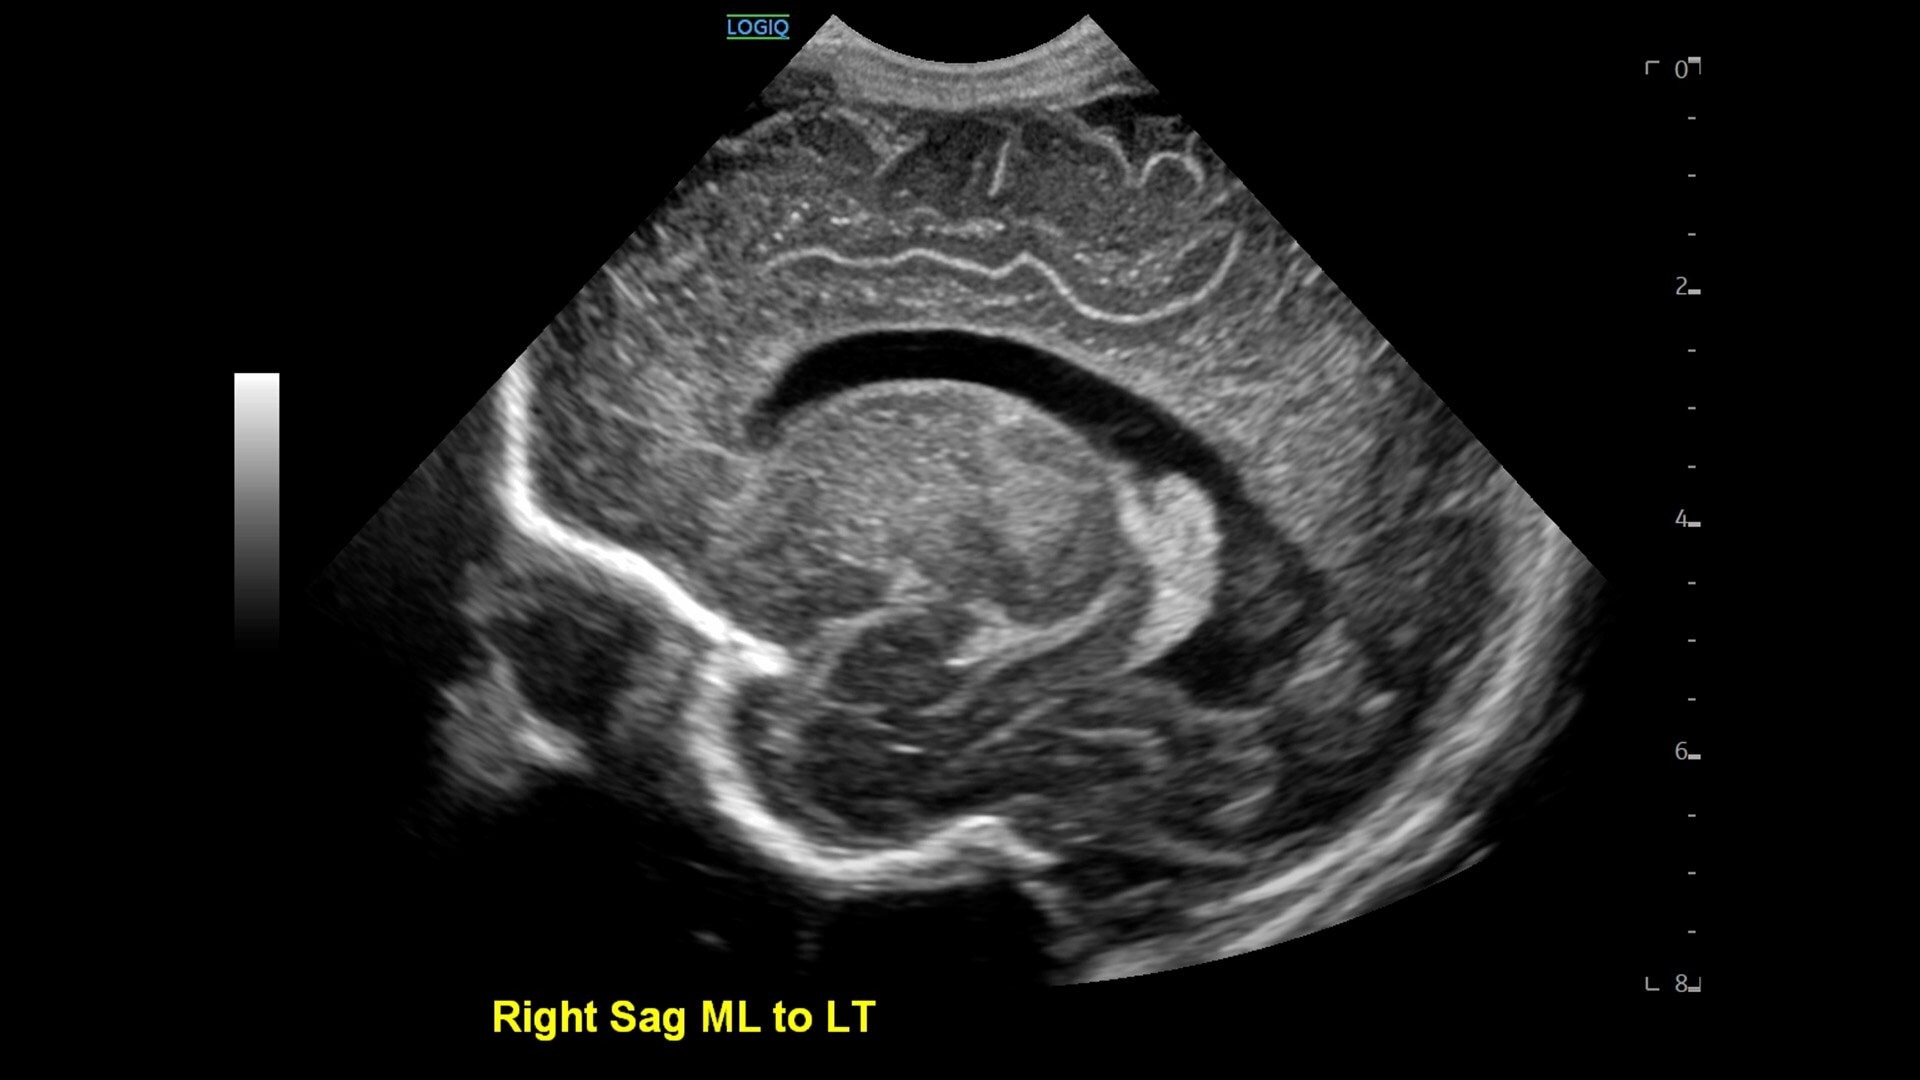

• cSound™ Architecture delivers exceptional clarity and resolution from near field to depth—with all pixels in focus

• 2D shear wave elastography with quality map provides quantitative insight into tissue elasticity—helping you assess different structures with confidence